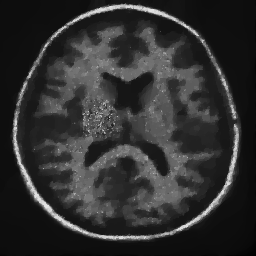

4.1. Uniform Gaussian noise

In this first experiment, we consider the denoising problem with brain scan images. The first set consists of images of pixels and Gaussian noise with zero mean and variance . The original and noisy images are shown in Figure 4.1. The domain decomposition-semismooth Newton algorithms run with the parameter values , , and . The results are shown in Figure 4.2. From the surface representation of , we can observe that is continuous and its shape is related to the one of the original image. In particular, the regularization is stronger in homogeneous regions in the image, and weaker where the image intensity undergoes variations on a smaller scale.